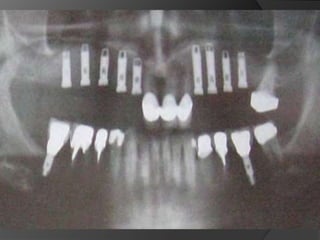

Diagnóstico y Planificación MultidisciplinariaHistoria ClínicaAnamnesisFotografía clínica Montaje modelos de estudioEncerados DiagnósticosEvaluación Radiográfica Radiografías PeriapicalesRadiografía PanorámicaEvaluación DentalEvaluación PeriodontalEvaluación EndodónticaEvaluación OclusalEvaluación Articular?

EVALUACIÓN DE PILARESProporción corona-raizConfiguración de la raízZona del Ligamento Periodontal (Ley de Ante)

Tylman: afirmó que dos dientes pilares son capaces de soportar dos póntIcos.Johnston y col.: LEY DE ANTELa superficie radicular de los dientes pilares, con soporte óseo periodontal, debe ser mayor o igual a la de los dientes a sustituir con pónticos